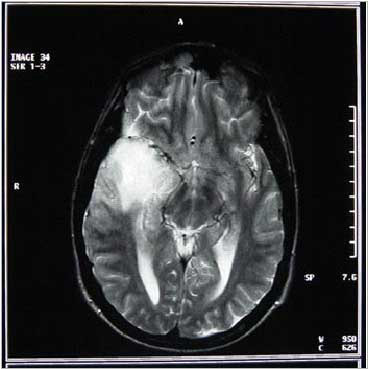

Cosa si intende con il termine Diagnostica per Immagini?

Con Diagnostica per Immagini (o imaging o imaging biomedico) ci si riferisce al processo attraverso il quale è possibile osservare un'area di un organismo non visibile dall'esterno.